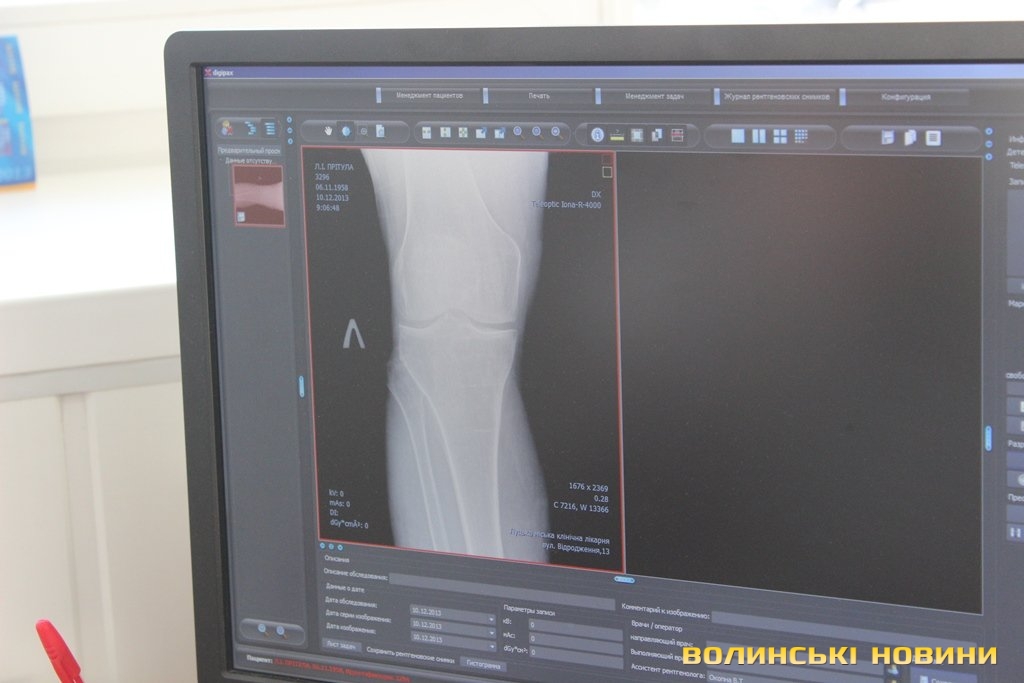

Травмовані заходять по черзі, але людей з різким болем пропускають першими. До слова, нещодавно тут почали працювати на новій цифровій апаратурі, для якої не потрібні одноразові плівки та й опромінювання менше. Рентген-лаборант Валентина Окопна каже: «Це пришвидшує прийом травмованих, бо ж не доводиться чекати, як в старинку, півгодини на результат сканування. Тепер рентгенівські результати миттєво отримує лікар на своєму комп’ютері, де може знімок збільшувати в рази і детально розглядати».